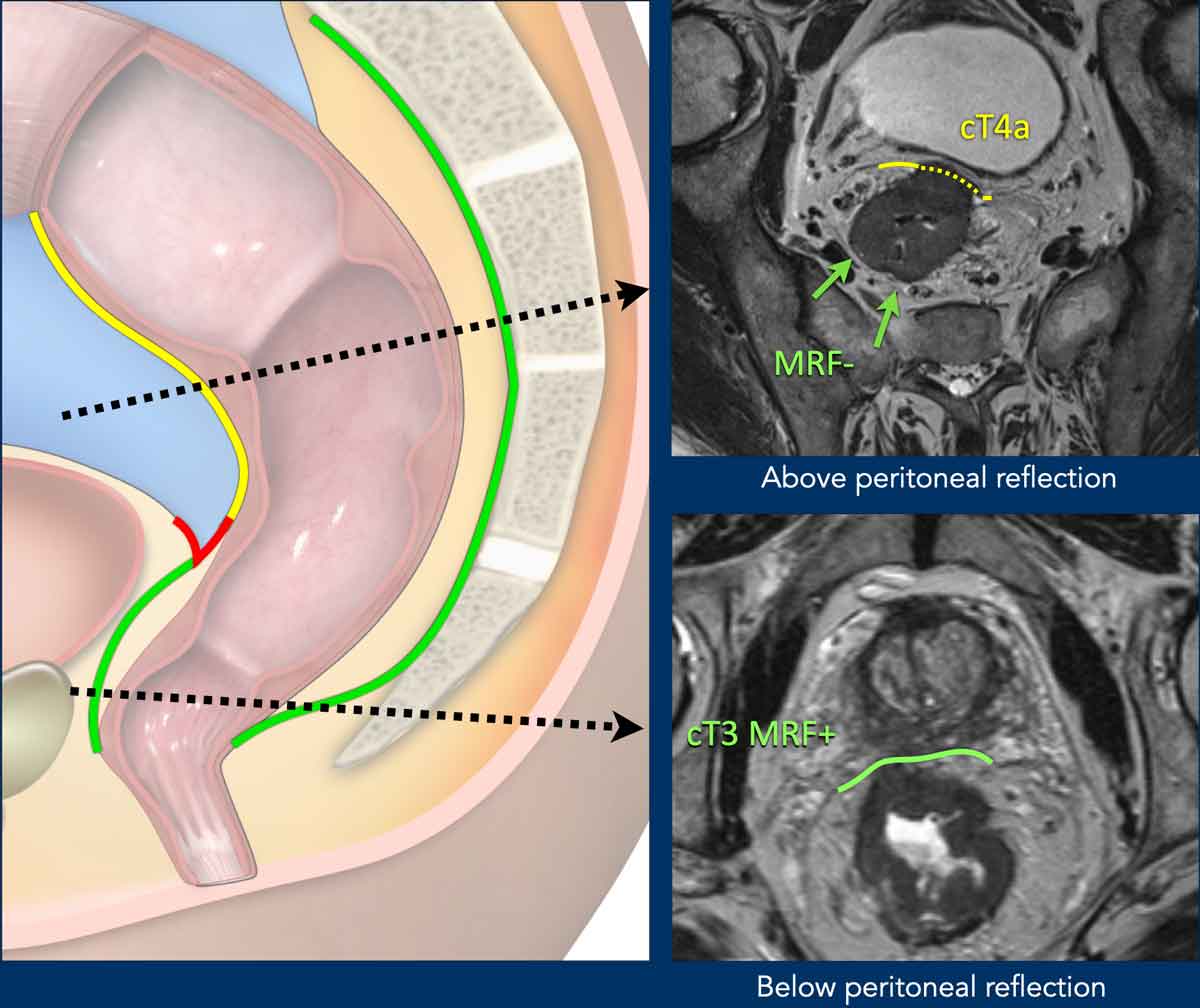

Mesorectal fascia vs. Peritoneum

Anatomical Coverage:

• Low rectum: Fully enclosed by the mesorectal fascia (MRF, green line).

• Middle rectum:

• Posterior/lateral: Covered by MRF

• Anterior: Covered by peritoneum (red line, peritoneal reflection)

• High rectum: Peritoneum extends anteriorly and laterally (yellow line); MRF covers only the dorsal mesorectum.

Clinical Significance:

• MRF invasion: Classified as T3 MRF+

• Peritoneum invasion: Risks peritoneal tumor spread; staged as T4a

Pitfall: Distinguishing MRF vs. Peritoneal Invasion in Anterior Tumors

Key Principle:

• Anteriorly, MRF invasion can only occur in tumors below the peritoneal reflection, reported as T3 MRF+

Anterior tumors above the peritoneal reflection that invade the peritoneum should be reported as T4a MRF

• Posteriorly, the MRF extends above the level of the peritoneal reflection. Simultaneous involvement of the MRF (posteriorly) and peritoneum (anteriorly) can occur, which should be reported as T4a MRF+

Image Examples

cT4a MRF– (Upper Image):

• Upper rectal tumor, above the peritoneal reflection

• Peritoneal involvement (dashed yellow line)

• No MRF involvement

cT3 MRF+ (Lower Image):

• Distal rectal tumor, below the peritoneal reflection

• Anterior MRF involvement (green line)

• No peritoneal involvement